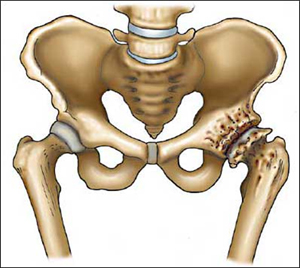

Οστεοαρθρίτιδα Ισχίου

Η άρθρωση του ισχίου είναι μία απο τις πιό συνηθισμένες εστίες ανάπτυξης οστεοαρθρίτιδας.Η οστεοαρθρίτιδα είναι η νόσος κατά την οποία εμφανίζεται προοδευτική καταστροφή του αρθρικού χόνδρου (του προστατευτικού δηλαδή περιβλήματος των οστών).

Κλινικώς διαπιστώνεται περιορισμός στις κινήσεις της άρθρωσης κυρίως της απαγωγής και έξω στροφής με αποτέλεσμα σε προχωρημένα στάδια το σκέλος να παίρνει ανώμαλη θέση χαρακτηριστική για την πάθηση, δηλαδή βρίσκεται σε κάμψη, προσαγωγή και εξωτερική στροφή. Η διάγνωση βασίζεται στην κλινική εικόνα και τον ακτινολογικό έλεγχο.

Τα κλασσικά ακτινολογικά ευρήματα που επιβεβαιώνουν την διάγνωση είναι:

- Μείωση του μεσοαρθρίου διαστήματος (δηλ. τού κενού που φαίνεται ανάμεσα στα δύο κόκκαλα)

- Σκλήρυνση του υποχονδρίου οστού – φαίνεται στις ακτινογραφίες σαν μια περιοχή πιο άσπρη απ’ ότι θα έπρεπε

- Μικρές κύστες στην περιοχή του υποχονδρίου οστού

- Οστεόφυτα στις παρυφές των αρθρικών επιφανειών